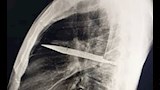

في واقعة طبية نادرة، اكتشف أطباء في تنزانيا شفرة سكين معدنية كبيرة مستقرة داخل تجويف صدر رجل يبلغ من العمر 44 عاما، بعد مرور ثماني سنوات على تعرضه لطعنات متكررة دون أن يعلم ببقاء الشفرة في جسده.

وأظهرت الفحوص السريرية أن الجزء الأيمن من صدره لا يتمدد بالكامل أثناء التنفس، فيما كشفت الأشعة السينية وجود شفرة سكين كبيرة عالقة في تجويف الصدر، ممتدة من الظهر إلى مقدمة القفص الصدري، ومحاطة بطبقات من القيح والأنسجة الميتة.